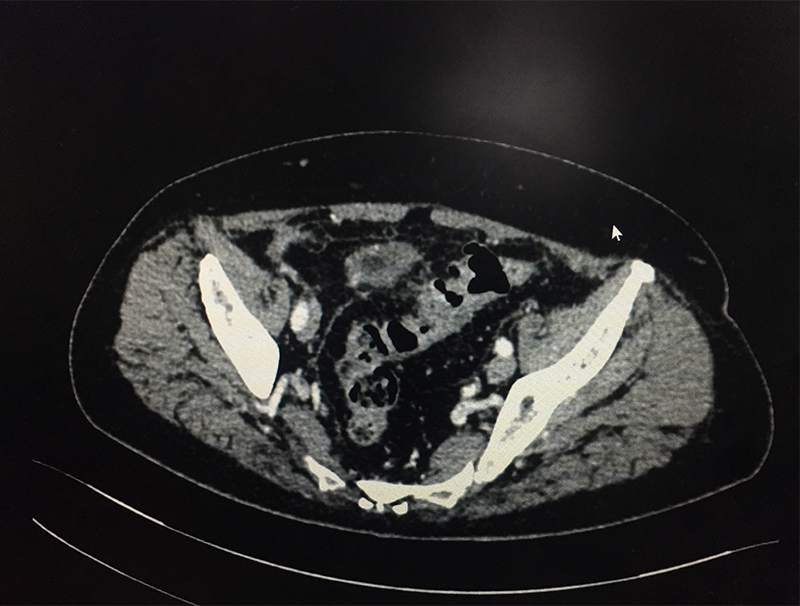

60 year old lady with an episode of sigmoid diverticular perforation with was managed with antibiotics and other supportive measures. A surgery was avoided at this time. She settled well, however started experiencing recurrent incapacitating abdominal pain due to sigmoid diverticular disease. A laparoscopic sigmoid colectomy and colorectal anastomosis was electively performed. She was discharged on postoperative day 5. She is now completely pain and symptom free.

When a patient with acute abdominal pain is diagnosed (clinical suspicion) with a possible diverticulitis, he/she needs further investigations; blood & imaging study (CT scan of abdomen & pelvis) to confirm the diagnosis, rule out complications and plan the treatment based on the laid out guidelines. Most patients without complications & few with complications like contained perforation abscess are managed with antibiotics and occasionally with percutaneous drainage. Few patient require a laparoscopic lavage and drainage. Those with major perforation and fecal contamination require emergency surgery. It is done as an open procedure or by laparoscopic route depending on available expertise & patient condition. The involved sigmoid colon is resected and an end colostomy (bringing out the proximal end) is performed. The colon is reconstructed at a later date once patient has fully settled. If patient is too sick to tolerate a major surgery only a diverting colostomy (to bring the intestine lumen out on surface) is performed.